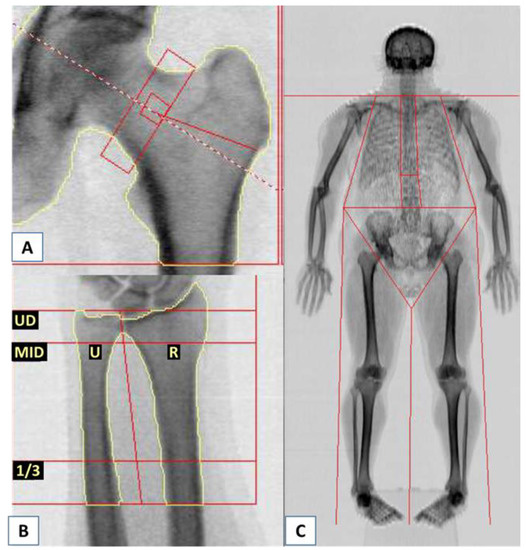

| (C). BMD Results Assessed by DXA at other Sites (Femoral Neck, Forearm, and Total Body). | |||||||

| Region | Area cm2 | BMC g | BMD g/cm2 | T-Score | PR% | Z-Score | AM % |

| Femoral neck | 6.33 | 5.87 | 0.927 | +0.0 | 100 | +0.8 | 114 |

| Ultradistal part of non-dominant (left) forearm; radius and ulna | 7.57 | 3.79 | 0.500 | −0.2 | 98 | +0.5 | 106 |

| 1/3 Distal part of non-dominant (left) forearm; radius and ulna | 6.28 | 4.79 | 0.762 | −1.1 | 92 | −0.5 | 96 |

| Total body | 2330.89 | 2502.36 | 1.074 | −1.3 | 90 | −1.0 | 91 |